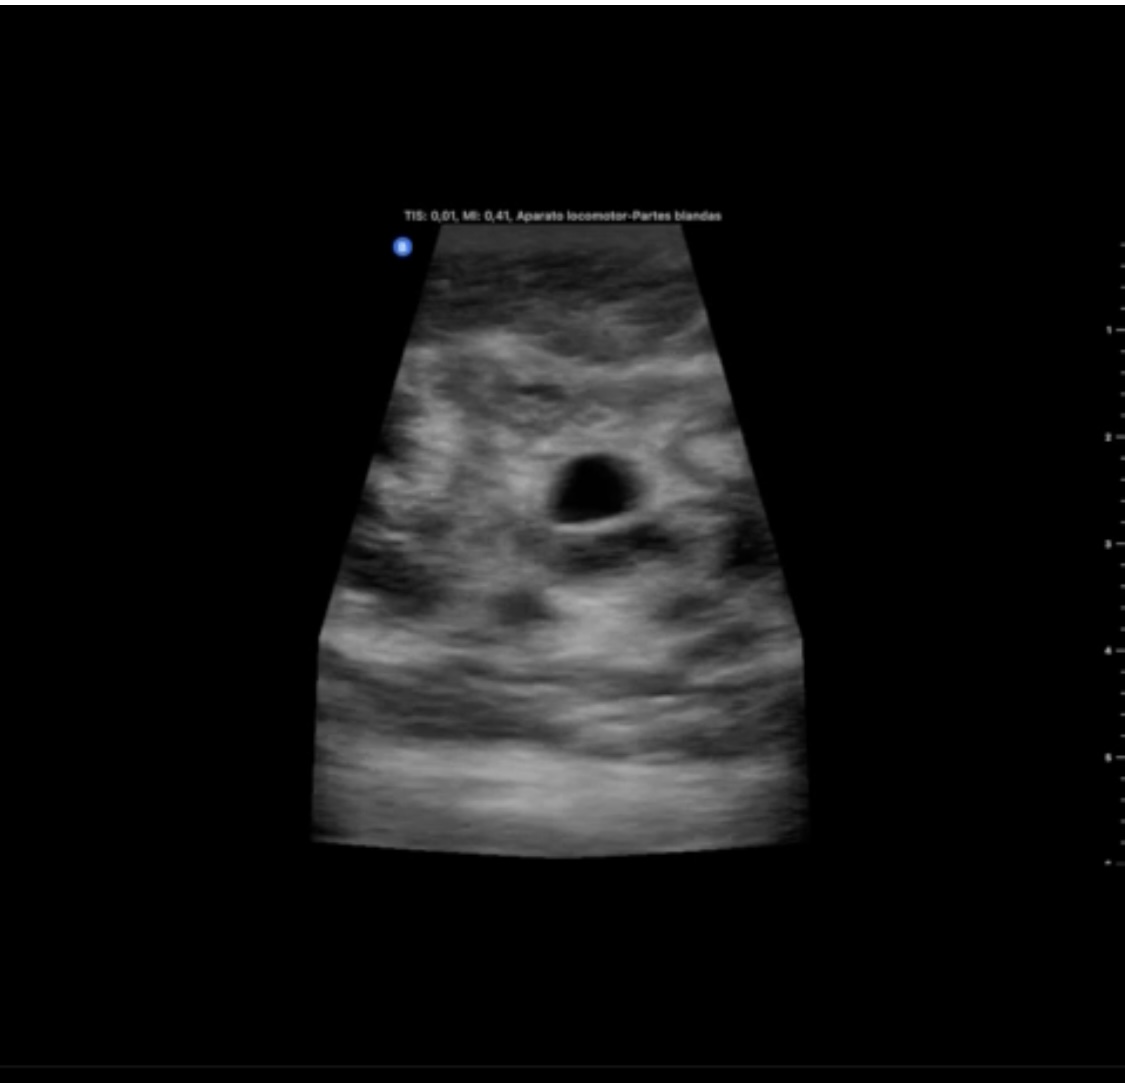

Hallazgos ecográficos

Se objetiva masa hipoecogénica respecto al tejido fibroglandular, heteroecogénica, mal delimitada, más alta que ancha y que no se modifica con la presión de la sonda. En regiones circundantes a la lesión se objetivan lesiones redondeadas, quísticas, que impresionan dilataciones de los conductos galactóforos.